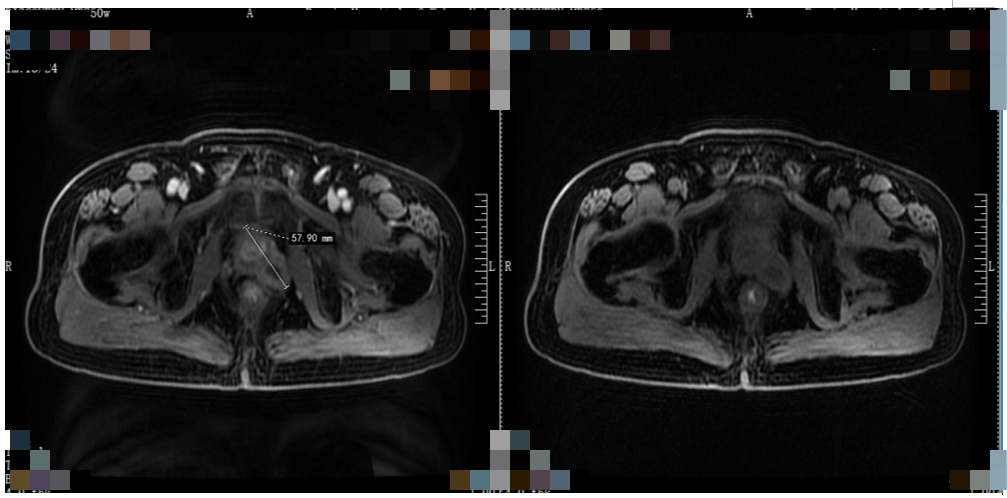

2020年7月因“体检发现PSA升高”就诊我院,磁共振检查提示前列腺外周带6点钟方向见结节样T2WI低信号,大小约6.6mm×14mm。

患者于1个月前行常规体检,发现PSA升高,为21.2ng/ml。病程中患者无排尿困难表现,无尿频、尿急、尿痛及肉眼血尿症状,无明显骨痛表现。患者为求明确诊治而来我院,磁共振检查提示前列腺占位性病变。

转移性前列腺癌(T3aN0M1b IV期B )。

治疗经过